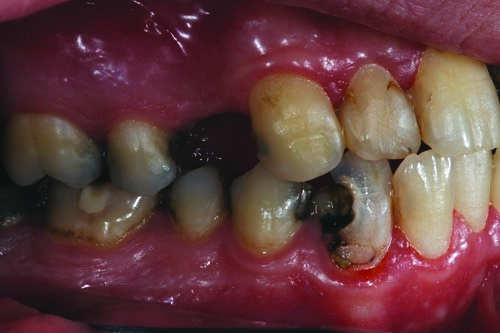

For this 31-year-old patient, an inability to afford or prioritize the care and treatment of his visibly damaged and decayed teeth—combined with a longtime fear of going to the dentist—led to a mouthful of severely deteriorated dentition and a history of chronic periodontal inflammation, multiple recurrent decay and incomplete treatments.

Over the years, friends, family members and co-workers would occasionally comment about his smile and ask what he was doing to fix it. Although he had regular cleanings every six months until he was in middle school (when his mother was in charge of his appointments), as he grew older he didn’t develop a regular brushing habit. As the cavities developed more frequently—and despite the use of nitrous oxide—his dental visits became increasingly unpleasant.

Fig. 2: Close-up retracted facial view of the patient’s upper and lower arches reveals extensive decay, missing teeth and obvious gingival inflammation.

Fig. 3: The preoperative right lateral view shows evidence of the failing mesial/occlusal/distal (MOD) amalgam restorations in teeth #2, #4, #5, #29, #30, #31 and #32, as well as the need to replace missing tooth #3.

Fig. 4: The preoperative left lateral view reveals that any treatment undertaken should address the patient’s numerous missing teeth, including #12, #15, #16 and #17 and multiple MOD amalgam restorations on teeth #13, #14 and #18 through #21.

Fig. 5: Close-up retracted view of the maxillary central and lateral incisors. Examination revealed that teeth #7 and #8 presented carious lesions and periapical periodontitis (PAP) that would require root canal therapy. Tooth #10 had previously undergone root canal therapy, but no post or core had been placed.